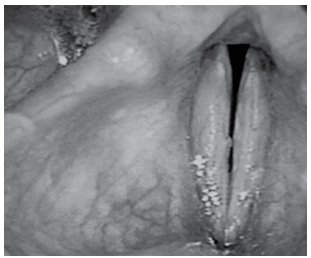

Avalie cuidadosamente, a seguir, a imagem de uma paciente de 41 anos com disfonia funcional.

Enunciado 4258529-1

(Mara Behlau, Voz: o livro do especialista)

A figura é compatível com uma fenda